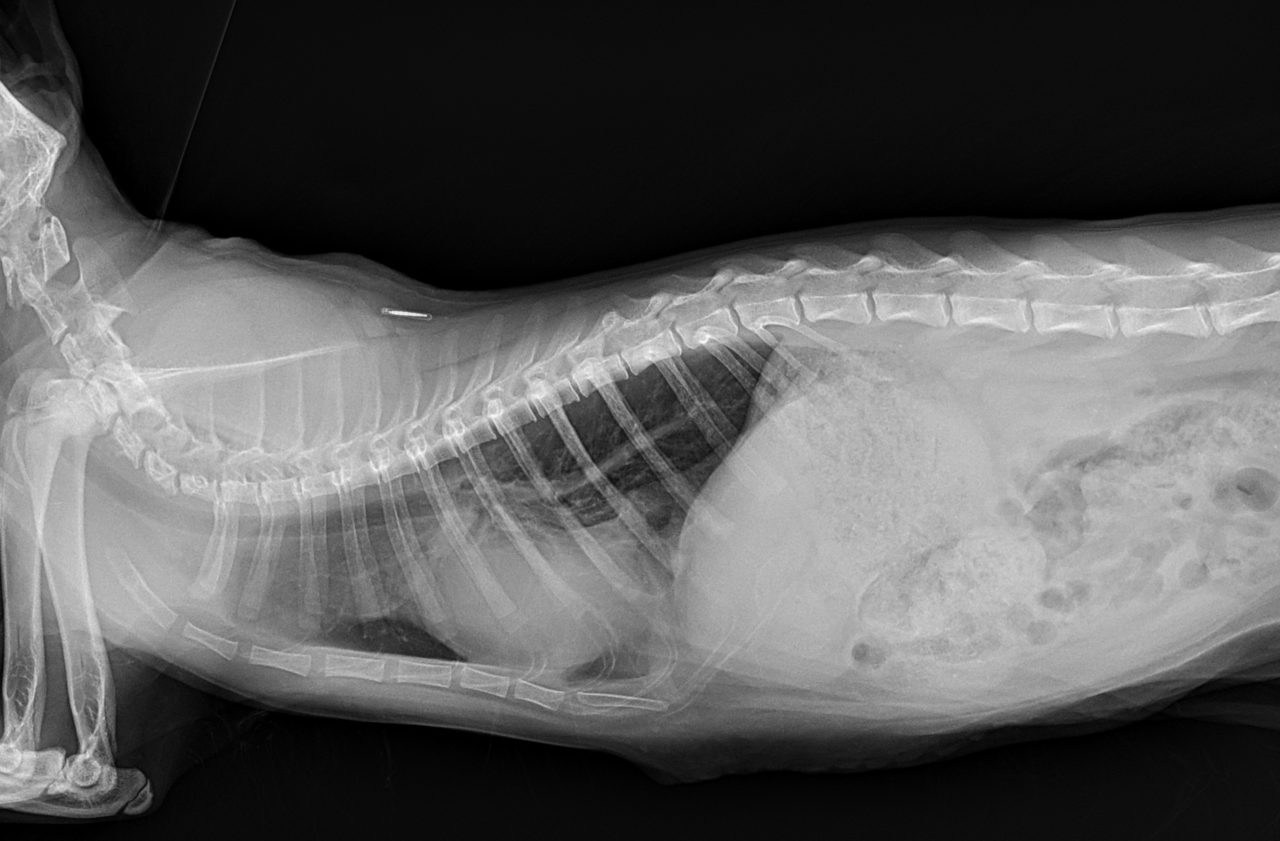

先天性心嚢横隔膜ヘルニア

若い猫が、普段はとても元気だけど、遊んだ後などに咳をする。呼吸が早くなる時がある。などの呼吸器症状で主治医を受診しました。エックス線検査の結果、心嚢横隔膜ヘルニアと診断されました。主治医より、外科的な対応のため紹介受診となりました。腹部正中切開の後、心嚢内に逸脱した、肝臓、胆嚢、小腸を腹腔内に戻し、横隔膜を再建しました。術後には、再拡張性肺水腫という病態が発生する可能性があるため、24時間体制で、患者さんを見守ります。幸い、肺水腫の傾向はみられず、5日目に無事に退院となりました。周術期には一時的に低酸素症に陥ったり、二酸化炭素濃度が上昇したりと、不安定な場面もありましたが、小さな体で本当によく頑張ってくれました。これで、普通の子猫としてどんどん大きく成長してくれると思います。本当によかった。